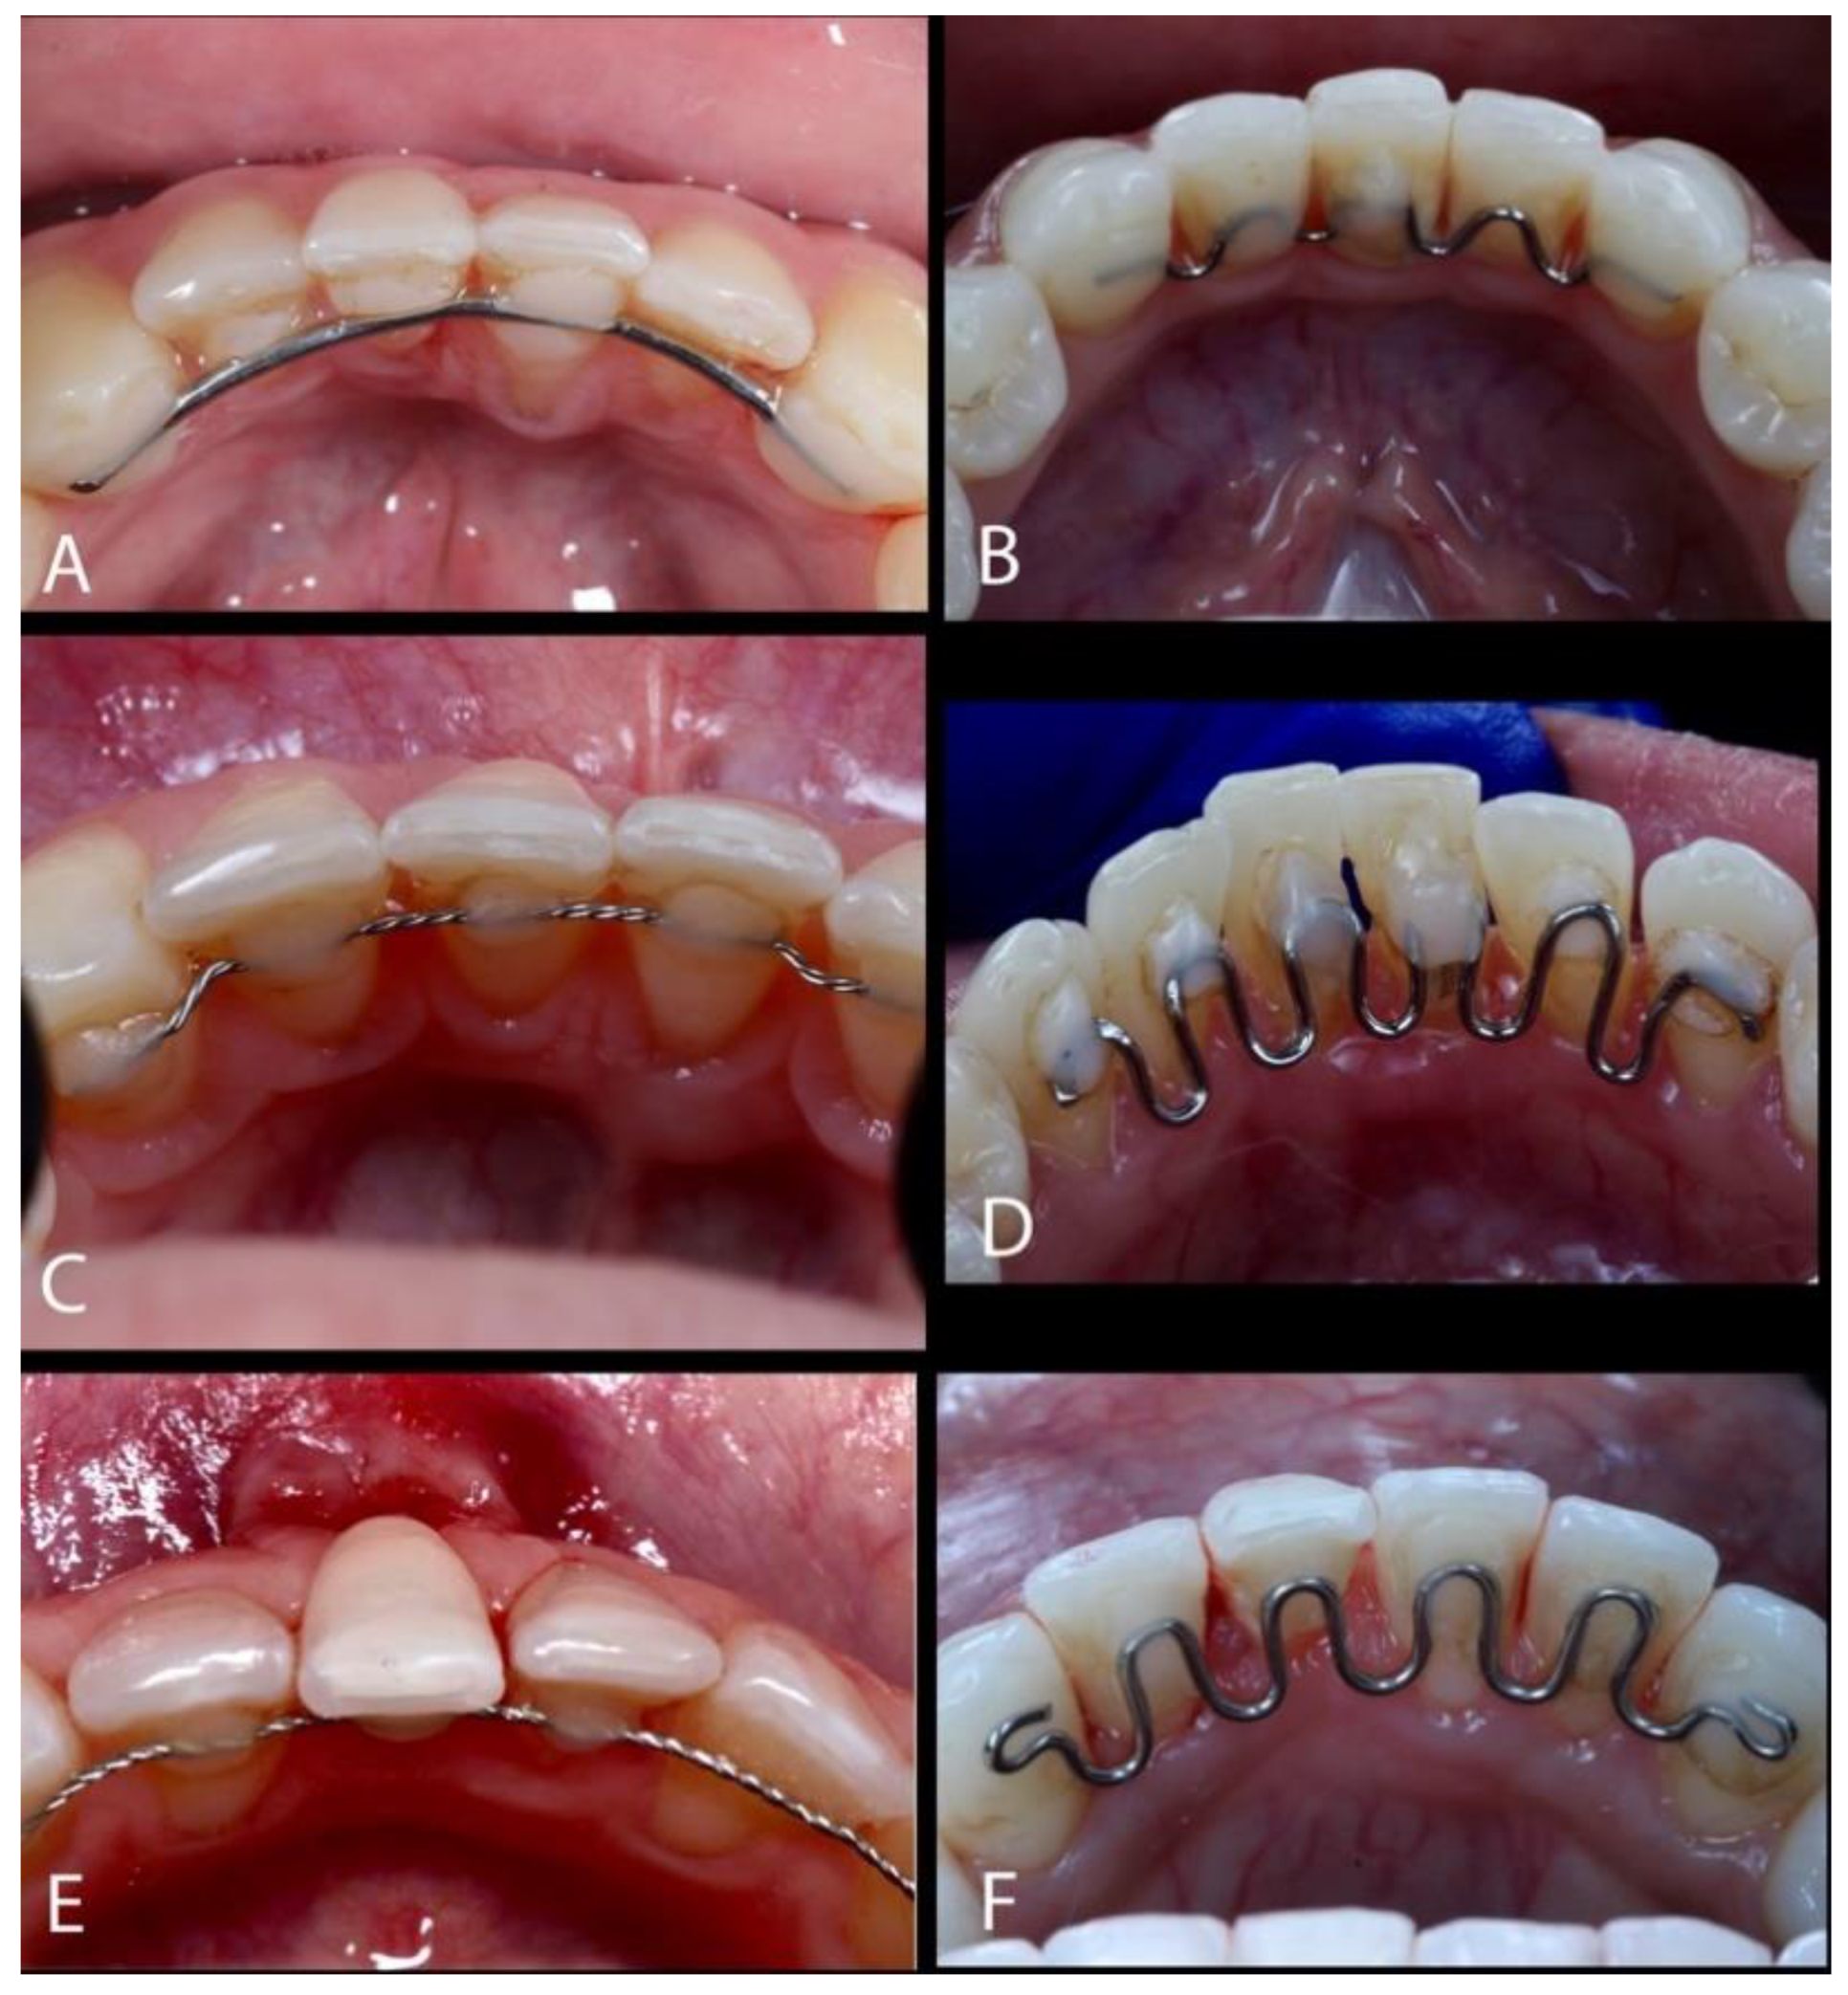

The Treatment of Gingival Recessions in the Lower Anterior Region Associated with the Use/Absence of Lingual-Fixed Orthodontics Retainers: Three Case Reports Using the Laterally Closed Tunnel Technique and Parallel Incision Methods

- Sculean, A.; Allen, E.P. The Laterally Closed Tunnel for the Treatment of Deep Isolated Mandibular Recessions: Surgical Technique and a Report of 24 Cases. Int. J. Periodontics Restor. Dent. 2018, 38, 479–487. [Google Scholar] [CrossRef] [PubMed]

- Kahn, S.; Araujo, I.T.E.; Dias, A.T.; Souza, A.B.; Chambrone, L.; Fernandes, G.V.O. Histologic and histomorphometric analysis of connective tissue grafts harvested by the parallel incision method: A pilot randomized controlled trial comparing macro- and microsurgical approaches. Quint. Int. 2021, 52, 2021. [Google Scholar]